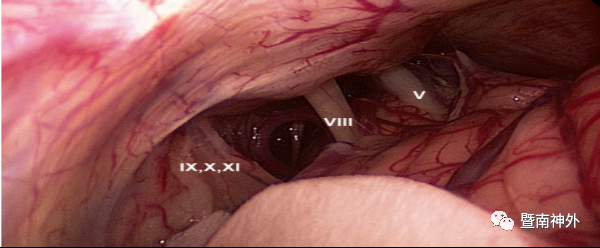

释放脑脊液,暴露桥小脑区,可见肿瘤基底位于岩骨面

电灼肿瘤的基底,显露小脑幕与岩骨面肿瘤

肿瘤对岩静脉有包裹,分离肿瘤,保护岩静脉

分离肿瘤与后组颅神经